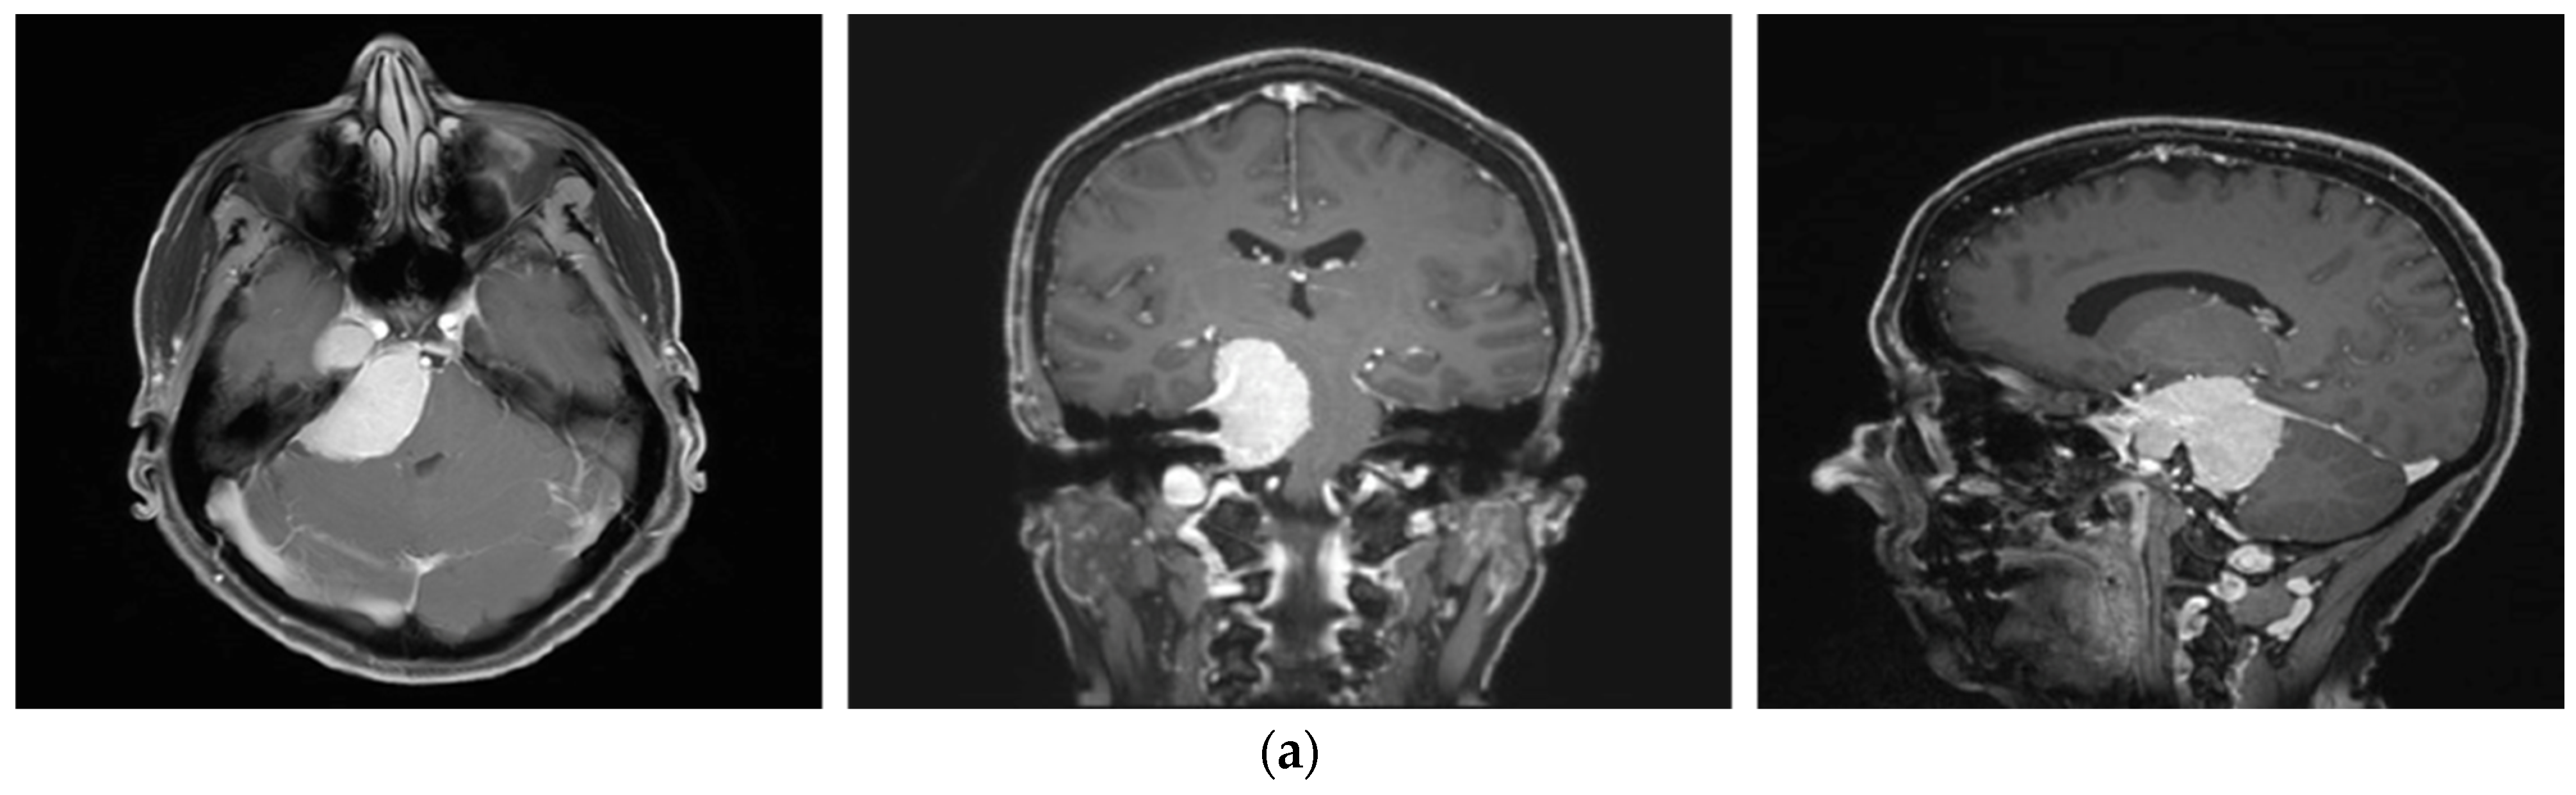

A 58-year-old female presented with progressive headache, difficulty swallowing, diplopia, hearing loss, and reduced face sensitivity on the right side (Figure 4). Elective craniotomy and AHSA-assisted tumor resection were performed. The patient underwent hypofractionated radiosurgery (5 × 5 Gy) of the residual meningioma one year after tumor resection.

Figure 4.

Second representative case of AHSA-supported tumor resection. (a) MRI imaging of petroclival meningioma (axial, coronal, sagittal). (b) Depiction of preoperative tumor volume (orange) and planned residual tumor volume (red). (c) AHSA summary table showing the stereotactic radiation constraints for the preoperatively planned residual tumor volume. With this plan, conventional fractionation and hypofractionation were feasible with effective tumor coverage.